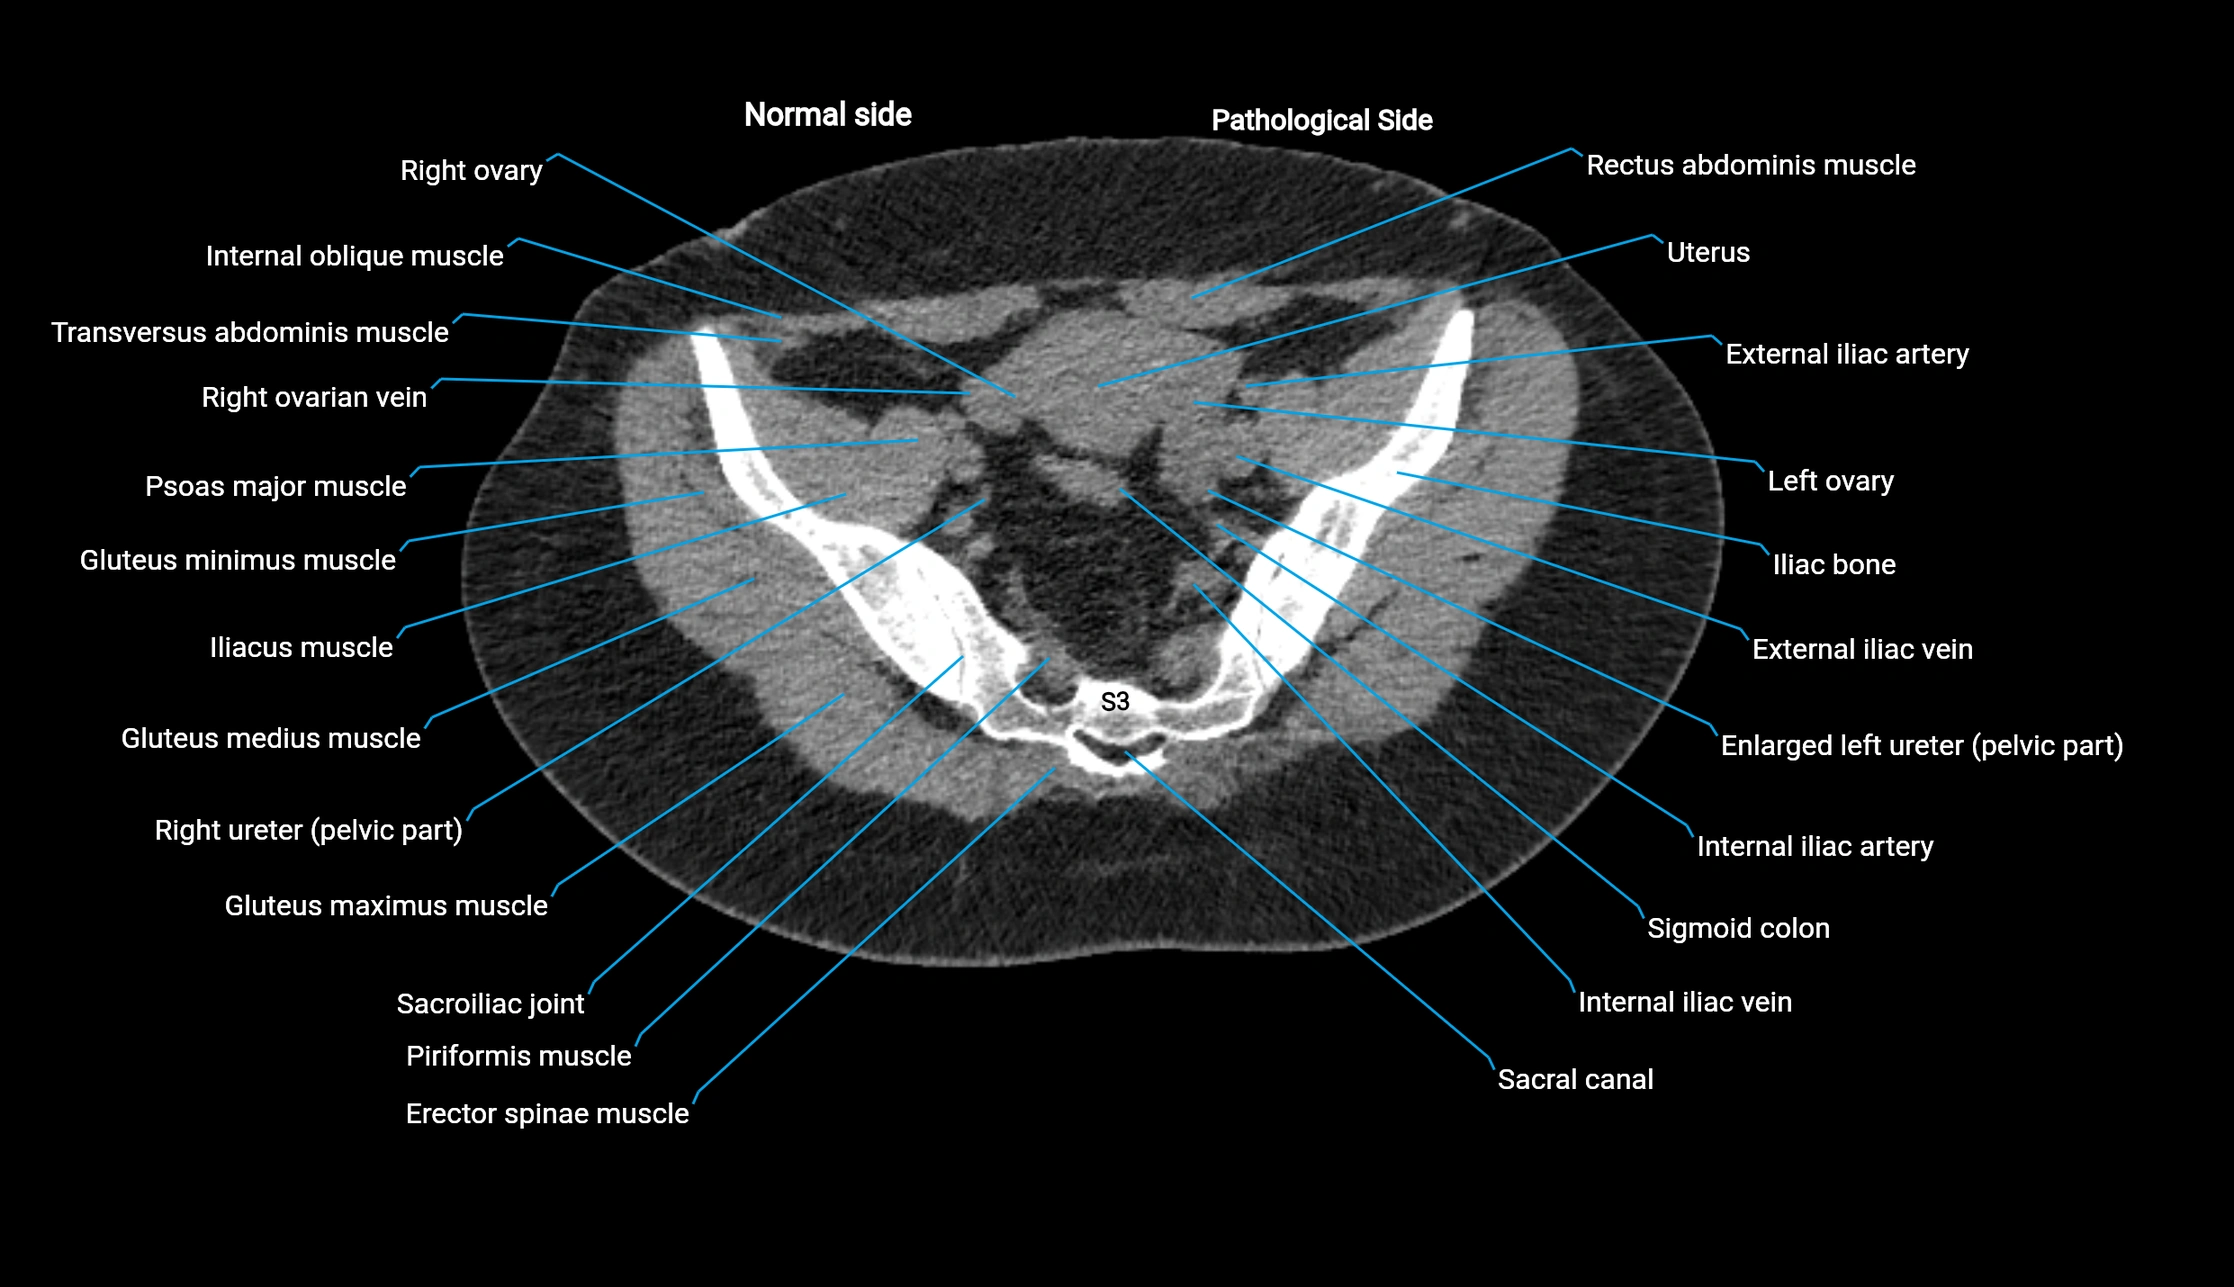

CT image

image